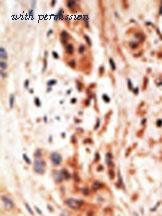

- APOBEC3A antibody